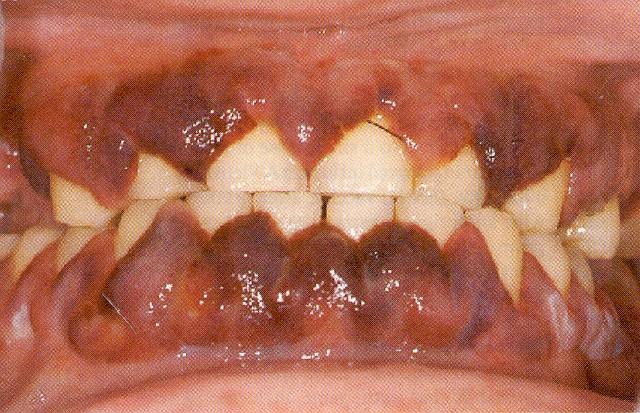

The presented case had gum invasion with myeloblasts (Panel A) and retinal Roth

Panel A.

The patient's gums have been invaded with myeloblasts. This is an important sign of AML and should prompt an immediate examination of a peripheral blood smear in both pediatric and adult patients.